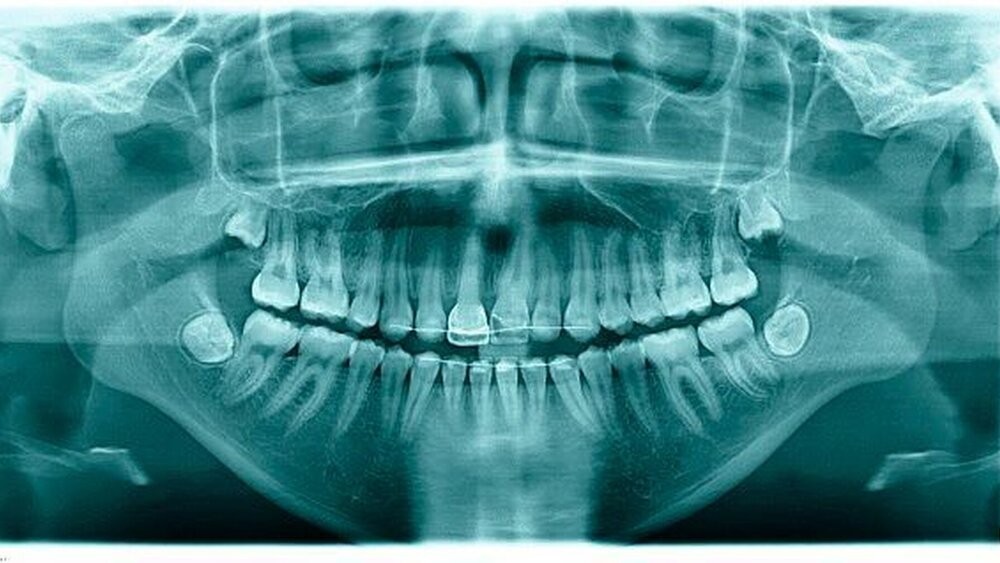

Bei anamnestischem und/oder klinischem Verdacht auf ein dentales Trauma soll eine bildgebende Diagnostik erfolgen (Zahnfilm, Orthopantomogramm, gegebenenfalls ein DVT).

Im Fall der Intrusionsverletzung des Zahnes 21 bei einem siebenjährigen Kind (Abbildung 1) würde im Rahmen der Weichteilversorgung die chirurgische Reposition als sofortige Dekompressionsmaßnahme des Zahnes 21 gleich mit durchgeführt werden. Denn im Rahmen der Sofortversorgung lässt sich der Zahn 21 leicht mit der Zange fassen und wieder in Okklusionsposition einstellen – gefolgt von flexibler Schienung für zehn Tage. Alternativ steht die schrittweise kieferorthopädische Extrusion zur Verfügung. Eine Schädigung des Zahnkeims ist bereits durch die Art des Zahntraumas zu erwarten. Mit erhöhter Wahrscheinlichkeit handelt es sich dabei um eine Ankylose des Zahnes mit zusätzlicher vertikaler Wachstumshemmung.

Regelmäßige Röntgenkontrollen sind hier erforderlich, um eine endodontische Versorgung des Zahnes nicht zu versäumen (nähere Details siehe LL-Text). Bei mittleren und schwerwiegenden Intrusionen ist in den meisten Fällen – unabhängig vom Wurzelwachstum – mit einer Obliteration oder Nekrose des Pulpagewebes zu rechnen [Humphrey, 2003]. Bei fortschreitender Resorption, Ankylose oder Entzündungszeichen kann es zum zeitnahen Verlust des Zahnes kommen.